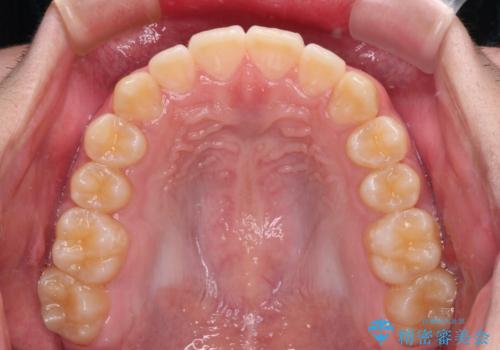

しっかり使って短期間で治療 インビザラインによる叢生解消

「しっかりと装着する」が実行でき、高校3年生の秋には治療を終えることができました。

入試時期に入ると、後戻り防止のリテーナー装着が疎かになる可能性があったり、リテーナーが壊れてしまった場合すぐに来院できなかったりというリスクがあったため、下顎前歯の舌側をワイヤーで固定することとしました。